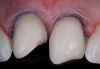

Fig 9. Preoperative view (Fig 9), preparation with composite block-out restoration (Fig 10), and final cementation of CL-IIb material (Fig 11) (final ceramic contour and stain by Steve Lee, CDT, MDC).

Figure 9

Fig 10. Preoperative view (Fig 9), preparation with composite block-out restoration (Fig 10), and final cementation of CL-IIb material (Fig 11) (final ceramic contour and stain by Steve Lee, CDT, MDC).

Figure 10

Fig 11. Preoperative view (Fig 9), preparation with composite block-out restoration (Fig 10), and final cementation of CL-IIb material (Fig 11) (final ceramic contour and stain by Steve Lee, CDT, MDC).

Figure 11